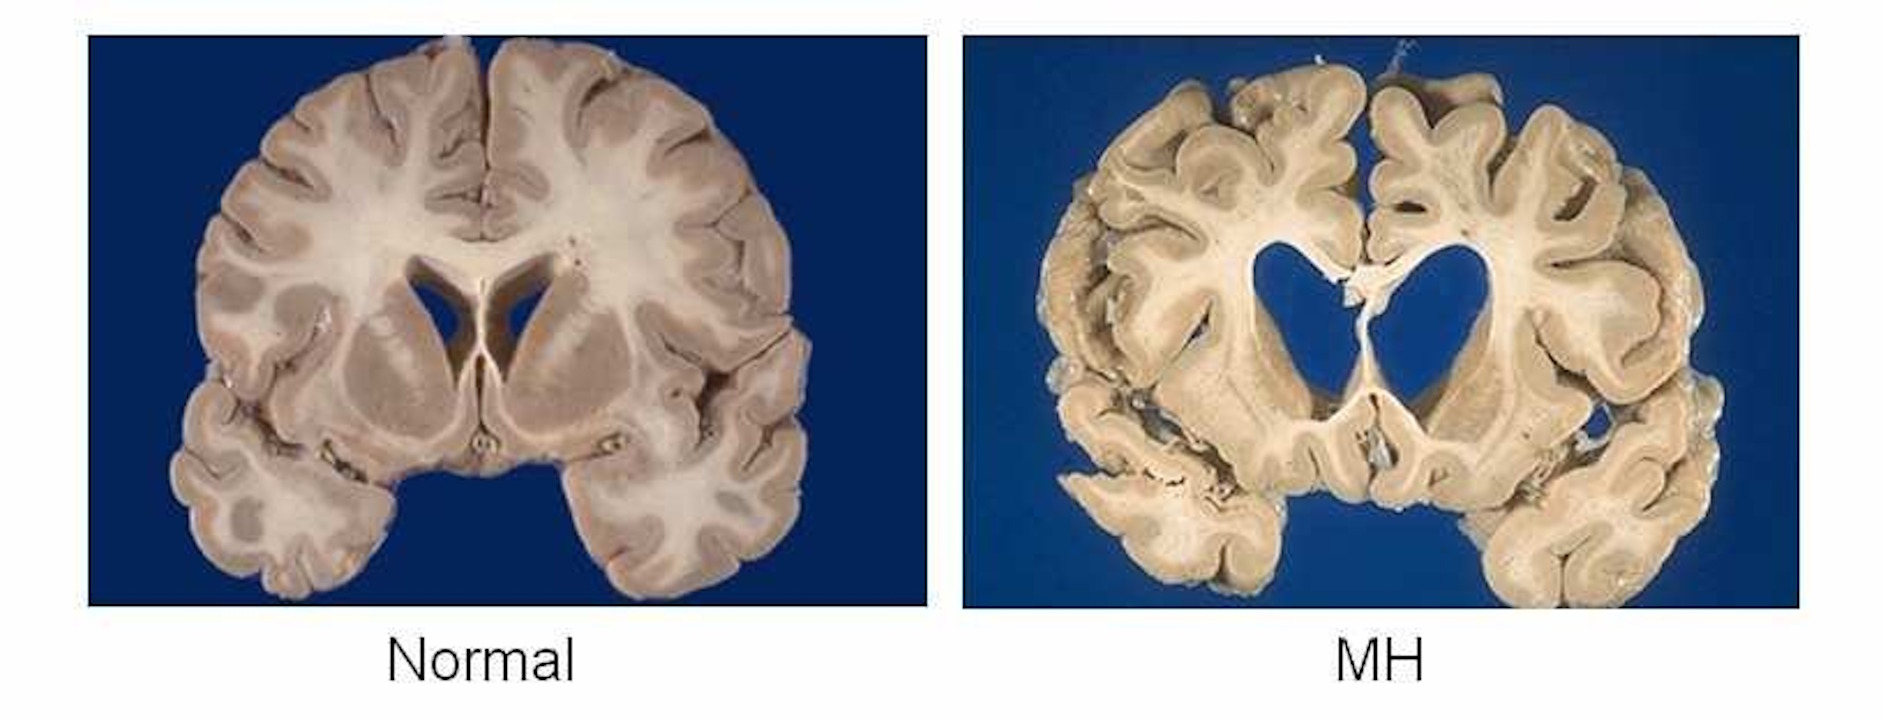

Відмирання нейронів смугастого тіла в людей з хворобою Гантінгтона (справа) порівняно зі здоровими (зліва). Camille Brochier

Хвороба Гантінгтона є спадковою і спричиненою мутацією в одному гені, який відкрили ще у 1993 році, але досі від неї не створили ефективної генної терапії. При цьому захворювання сильно впливає на поведінку, здатність до руху та розумові здібності пацієнтів, а середня тривалість життя після появи симптомів складає до 20 років. Тому науковці розробили терапію на основі здорової версії гена, яку доставили до клітин за допомогою частинок нешкідливого вірусу. А до ураженої хворобою ділянки мозку, смугастого тіла, частинки вірусу доставили за допомогою катетерів, які вводили в мозок.